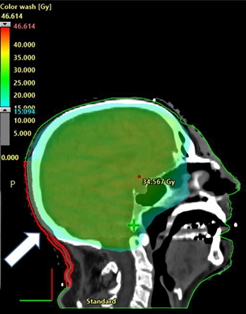

A 71-year old Caucasian male with metastatic melanoma required whole brain radiotherapy (WBRT). He was initially on combination immunotherapy with nivolumab and ipilimumab which was changed two months after WBRT to single agent nivolumab. He was treated with a hair-sparing protocol.9 The trial specific prescription delivered 30 Gy in 10 fractions to the whole brain as well as 40 Gy in 10 fractions via a SIB technique to two MRI detected asymptomatic brain metastases. The study delivered a lower dose to contoured superior (supscalp) and inferior (infscalp) scalp regions to try to spare scalp hair. The trial specific inferior scalp region (“inf scalp”) was a volume that included a hair bearing region that extended from a line 2 cm above the pinna to the hair line at the nape of the neck. The patient remained on nivolumab and 7.5mg of daily prednisolone throughout WBRT treatment. Figure 5 shows the hair colour prior to therapy. The original “inf scalp” volume (Figure 5B) received a maximum of 21 Gy, a minimum of 0.5 Gy and a mean dose of 11.7 Gy. One month post treatment, there was no change in hair colour but epilation in-field was apparent (Figure 5C). Hair below the arrows is the patient’s original hair colour prior to WBRT which retained its colour. At four months post WBRT, there was depigmentation of both the sup and inf scalp volumes. In order to be more precise about the hair colour change inferiorly, a new contour was created called “new infscalp”. This contour replicated the infscalp volume except that the lower border was on the line of the hair colour change, aligning it to the end of the WBRT field (Figure 5D). The dose was then recalculated from the original plan and a new dose volume histogram was produced (Figure 5F). The new “infscalp” volume (Figure 5B) received a maximum of 21 Gy, a minimum of 5 Gy and mean dose of 15 Gy (Table 2). Dosimetry of penumbral areas where the hair colour change was noted is detailed in Table 2.

Figure 5B Dosimetry on the midline sagittal planning scan from dose wash of 15 Gy of the Hair Spare protocol.9 Note the white arrow showing the trial specific infscalp volume which goes inferiorly to the hair line at the nape of the neck.

Figure 5E Dosimetry on the midline sagittal planning scan from dose wash of 5 Gy of the Hair Spare protocol. Note the diagonal white arrow showing the trial specific supscalp volume. The horizontal white arrow shows the new infscalp volume which goes inferiorly only to the level of the change in hair colour.